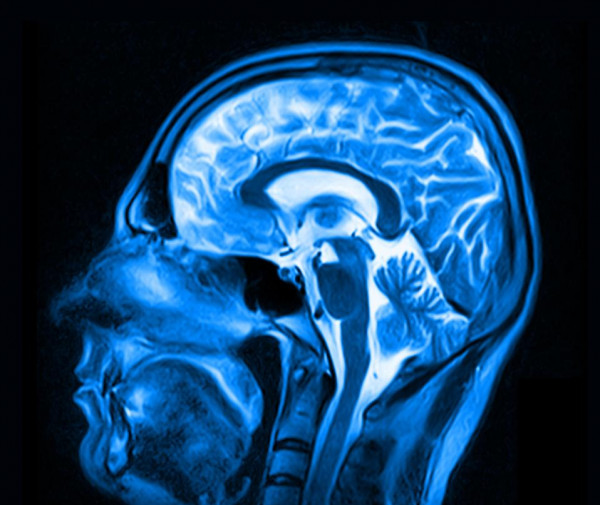

يعتزم علماء صينيون تطوير ماسحة مغناطيسية حديثة تبلغ قيمتها 100 مليون جنيه إسترليني، في محاولة للعثور على الروح البشرية داخل جسد الإنسان، بحسب ما أفادت صحيفة "ذا صن" البريطانية.

ويقول العلماء، إنهم يهدفون إلى بناء أقوى جهاز تصوير بالرنين المغناطيسي في العالم، والذي قد يكون في يوم من الأيام قادر على المساعدة في الإجابة على أحد الأسئلة المهمة في الحياة.

ويرى أحد كبار العلماء المنوط بهم هذا العمل في مختبر في شينزين، أن الماسح الضوئي "سيحدث ثورة في دراسات الدماغ"، وأضاف عالم آخر: "قد نلتقط لأول مرة صورة كاملة عن الوعي البشري أو حتى جوهر الحياة نفسها"، مستطرداً: "يمكننا تحديدها وشرحها من الناحية المادية الدقيقة تمامًا مثلما قام نيوتن وآينشتاين بتعريف وشرح الكون".

وكشفت معاهد شنتشن للتكنولوجيا المتقدمة، أنها أعطت الضوء الأخضر للبدء في المرحلة الأولى من المشروع، ويمكن أن تساعد التقنية الحديثة في دراسة وتشخيص الحالات العصبية التنكسية، بما في ذلك مرض باركنسون والزهايمر، وتستطيع ماسحات التصوير بالرنين المغناطيسي الحالية تصوير الكائنات التي يزيد حجمها عن 1 ملم فقط، ولكن الجهاز الجديد يهدف إلى تصوير الكائنات الأصغر بـ1000 مرة.